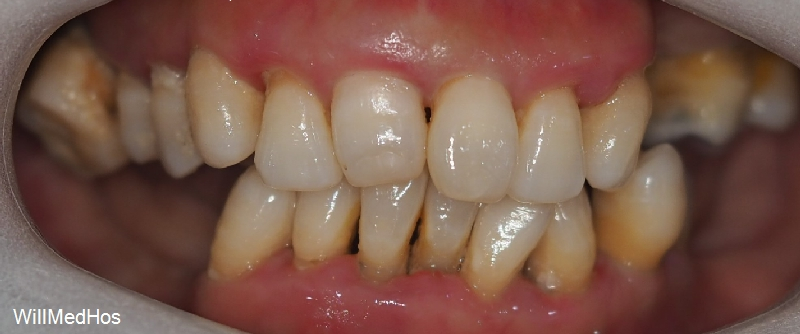

이미 자연 발치와 치과에서 발치 진단을 받으시고 발치 후 10년 가까이 치아들을

방치 해놓으신 상태라 위의 치아들이 정출되어 내려오기도 하고 관리가 아예 안되신 상태 이셨습니다.

상하악 전치부위와 소구치만으로 교합력을 견디기 어렵습니다.

왜냐하면 앞니부위와 어금니부위는 서로 상호 보완적인 관계에 있습니다.

위에 말씀 드린 부분을 상호보호교합이라고 부르는데요 .

이 교합 상태에서는 어금니가 수직 압력을 담당해 저작 시 앞니를 보호하고, 앞니는 측방(옆으로) 움직임에서 어금니를 보호하여 서로의 부담을 줄여 줍니다. 상호 보호 교합은 치아 마모와 턱관절에 가해지는 부담을 최소화하고, 안정적인 교합을 유지하는 데 중요한 역할을 합니다.

그런데 지금처럼 구치부가 모두 소실되어 교합이 무너지게 되면 전치부도 힘을 받게 되어 치조골이 소실됩니다 !!